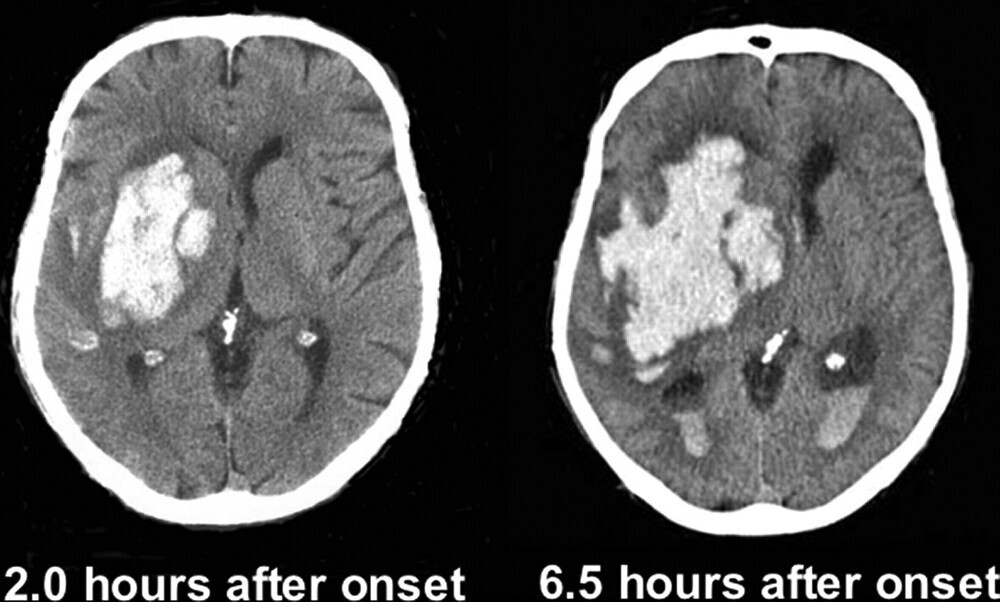

먼저 쉬운 개념부터 시작해보겠습니다. 뇌출혈은 그 이름에서 알 수 있듯이 뇌 내부에서 출혈이 발생하는 질환입니다. 즉, 뇌 혈관이 터져서 혈액이 뇌 내부로 흘러들어가는 것을 말합니다. 이 출혈은 외상이나 심혈관 질환 등의 원인으로 발생할 수 있습니다.

이렇게 말하면 뇌출혈과 뇌경색이 뇌졸중이라는 것을 알 수 있습니다. 그런데 사실 뇌출혈은 뇌경색이 진행된 후에 발생하는 경우가 많습니다. 하지만 뇌경색을 인지하지 못한 상태에서 갑작스럽게 혈관이 파열되어 뇌출혈이 발생할 수도 있으며, 고혈압과 같은 기저 질환을 가진 사람들이나 온도 변화가 급격한 겨울철에 혈압이 높아져 혈관이 터지기도 합니다.

요약하자면, 뇌졸중은 뇌 혈관의 문제로 인해 발생하는 질환을 의미합니다. 뇌출혈은 뇌 혈관이 터져서 출혈이 생기는 것이며, 뇌경색은 뇌 혈관이 막혀서 혈액 공급이 끊기는 것입니다. 이렇게 뇌졸중은 두 가지 형태로 구분할 수 있습니다.